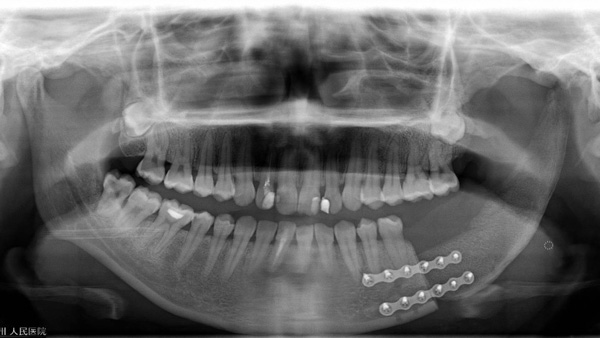

手術(shù)當天,口腔科手術(shù)團隊首先按照術(shù)前設(shè)計并3D模擬的截骨導(dǎo)板對下頜骨及腫瘤精準切除;再根據(jù)術(shù)前設(shè)計的髂骨截骨導(dǎo)板精準取骨和精準切割塑形拼接,后把移植骨的動脈和靜脈在顯微鏡下吻合到頸部的動脈和靜脈血管上,重建血循環(huán),恢復(fù)功能,經(jīng)過十多個小時的努力,終于圓滿完成了下頜骨缺損重建。

該例復(fù)雜的髂骨重建下頜骨手術(shù)得以成功實施,是柳州市人民醫(yī)院口腔科頜面外科團隊高超技術(shù)實力的證明,通過先進的輔助手段,讓很多傳統(tǒng)手術(shù)的方式發(fā)生了改變,不僅能為患者“治病”,還能滿足患者在頜面功能保留和美觀方面的需求,讓患者能夠高質(zhì)量回歸正常生活。